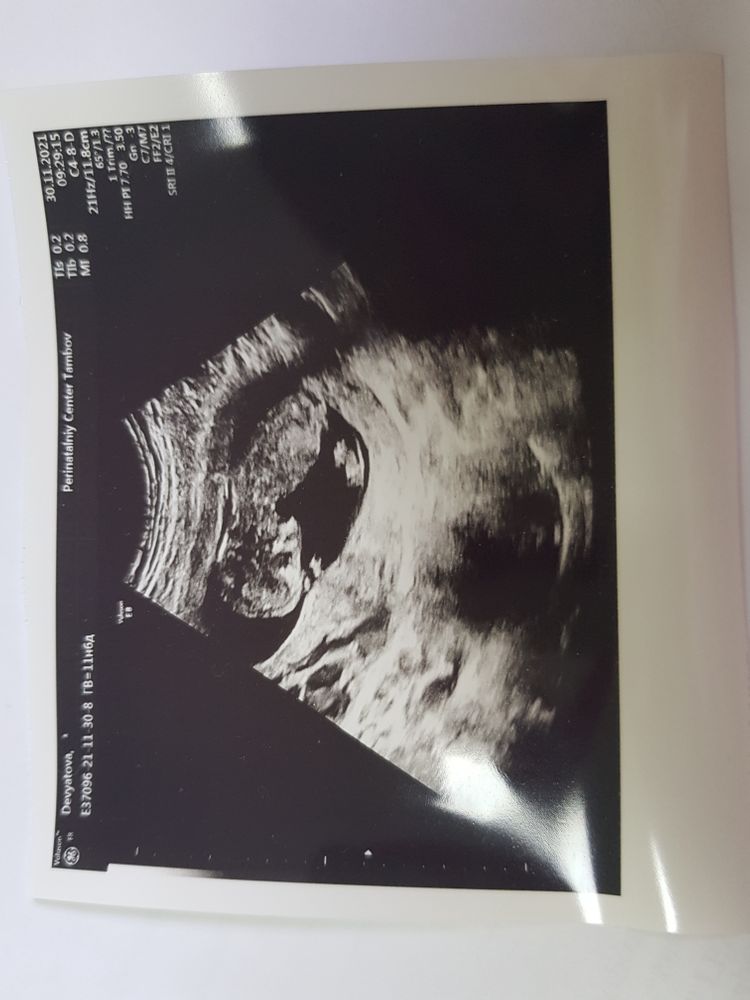

Фоточку взяла)